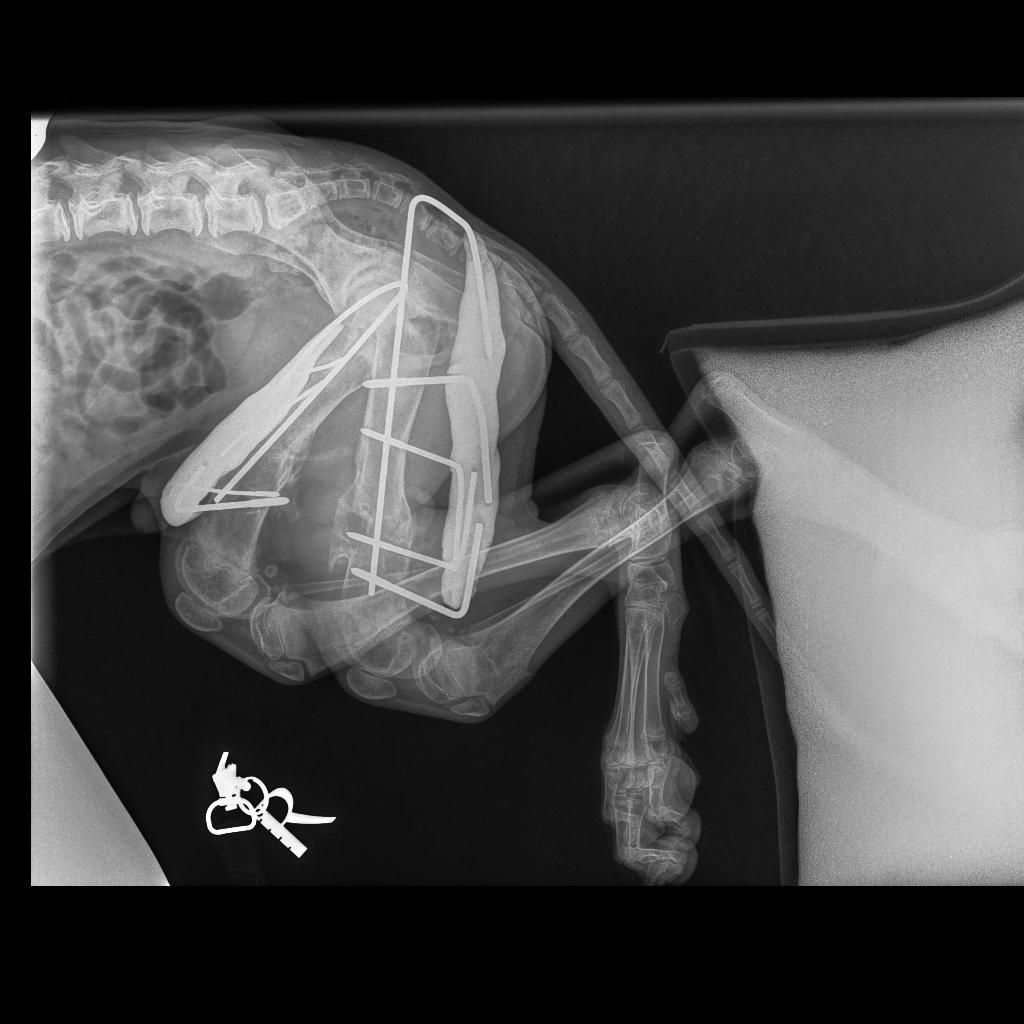

Die Fixateure sind raus, nun kann der Kleine ohne diese blöden Stangen sich bei Aliki bewegen. Er ist noch sehr vorsichtig, verständlich, schließlich muss er nun erst lernen, richtig zu laufen und Muskelmasse aufzubauen. Sein Freund Lenny wird ihm helfen, zusammen werden sie stückweise die Welt erkunden. Wer dabei helfen mag, dadurch, dass er/sie Schröder ein liebevolles Zuhause bietet, wird sicherlich nicht nur ein süßes Schlitzohr, sondern auch einen dankbaren Freund gewinnen. Gerade dieser kleine Kämpfer hat es verdient, mit Schmuseeinheiten überhäuft zu werden. 💙

Juli 2023

Arztbesuch.💉🚨

Aliki ist mit den beiden Hunden, Lenny und Schröder, nach Thessaloniki in die Tierklinik gefahren, da bei dem jungen Hund, wir erinnern uns, Schröder war als ganz junger Welpe von einem Auto überfahren worden, mit einigen Knochenbrüchen und zweifacher Operation, nun auch die Fixateure aus dem Becken entfernt werden konnten. Und bei dem kleinen Lenny wurde eine Biopsie gemacht, um die richtige Behandlung für den systemischen Lupus festlegen zu können. Beiden wünschen wir gute Besserung!